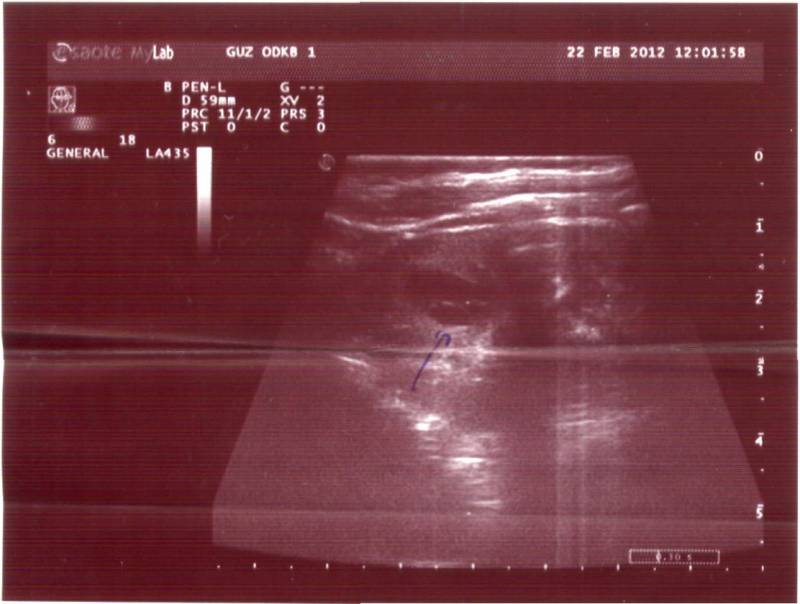

Здравствуйте. Моей дочке 10 месяцев. В месяц сделали УЗИ - поставили диагноз "простая солитарная киста". В дальнейшем находились под наблюдением нефролога и делали несколько УЗИ. На сегодняшни й день ставят диагноз "поликистоз, вторичный пиелонефрит". По анализу крови креатинин 29,4, мочевина 2,8. Напишите, пожалуйста, можно ли по снимкам определить вид поликистоза: детский или взрослый. Снимки выкладываю. Буду благодарна за высказанное мнение.

Добавлю последние три узи: Возраст 9 месяцев ПРАВАЯ ПОЧКА: визуализация затруднена из-за повышенной пневматизации кишечника, топография не изменена, физиологическая подвижность не нарушена, размеры: 67х29х23 мм, толщина паренхимы 11 мм. Контуры ровные, четкие, сохранены. Дифференцировка паренхимы и синуса нарушена. Интраренально лоцируются множественные неправильной формы анэхогенные образования с четкими контурами размерами до 5,5х9,3 мм. ЛЕВАЯ ПОЧКА: визуализация удовлетворительная, топография не изменена, физиологическая подвижность не нарушена, размеры 62х23х22 мм, толщина паренхимы 11 мм. Контуры ровные, четкие, сохранены. Рисунок интрарельных структур хорошо дифференцирован во всех отделах. Признаков дилатации визуализируемых структур коллекторной системы не выявляется. Дополнительные интра- и параренальные включения не определяются. НАДПОЧЕЧНИКИ: в проекции надпочечников дополнительные образования не определяются. ЗАКЛЮЧЕНИЕ: эхографическая картина поликистоза правой почки? Возраст 10 месяцев: ПРАВАЯ ПОЧКА увеличена: 6,5х3,9х4,0, структуры неровные, бугристые Л/ПОЧКА: нормальная 5,9х2,5х2,6 Кортико-медуллярная дифференцировка: .... (что-то тут не разборчиво написано) участки сохраненной паренхимы, справа меньше Эхоплотность справа значительно повышена, слпва умеренно повышена В структуре обеих почек ...(не понятно) участки кистозно-измененной ткаи по типу мультикопулярных кист, справа изменения более выражены. Лоханки с обеих сторон нормальные Признаки конкрементов отсутствуют ЗАКЛЮЧЕНИЕ: эхопризнаки кистозной дисплазии почек предположительно по рецессивному типу Возраст 1 г. 4 месяца: Положение правой и левой почек - обычное размеры: пр. - 67х32 мм, лев. - 68х34 Паренхима пр. - 13 мм, лев. 12 мм Чашечно-лохаочный комплекс: расширены чашечки (не могу разобрать что за цифры) но по-мойму вот так около 4,0-5,0 мм, слева 4,0-7,0 Лоханка справа 7,0 мм, слева 6,0 Мочеточники не изменены Патологических образований нет Надпочечники не визуализируются. ЗАКЛЮЧЕНИЕ: Эхогенные признаки ... (не поняла) желчного пузыря по гипомоторному (вроде так) типу (в умеренно выраженной степени) Признаки дисболической нефропатии. Рекомендуется консультация нефролога. Это было узи полностью внутренних органов, поэтому там и про желчный пузырь. Узист на словах мне сказал, что у него нарушен режим питания (это действительно было так, так как мы уезжали в другой часовой пояс) и что у него застужены ножки. Подскажите, пожалуйста, а вы что думаете про эти узи.

Похоже на взрослый поликистоз - но, конечно смотреть надо при лучшем разрешении, т.е. за экраном и важно знать ещё ряд параметров : 1) сколько кист в каждой почке, 2) их размер, 3)размер каждой почки, 4) есть ли изменения в печени.

Думаю. что необходимо сделать УЗИ в том медучреждении, где имеется нефрологическое отделение и детские нефрологи и затем очно проконсультировать с нефрологом - попросите, что бы врач, делающий УЗИ, распечатал картинку правой и левой почки - если Вы разместите здесь- фото или скан УЗИ-изображения - можно будет более предметно высказаться.